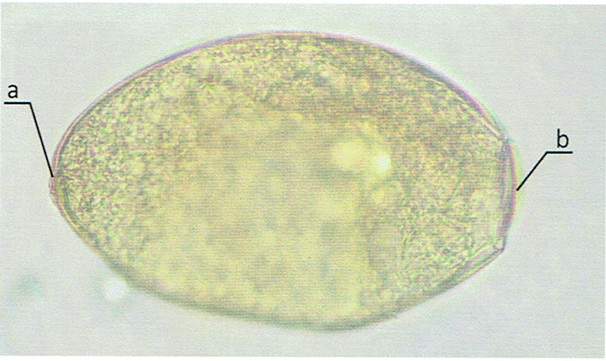

Fasciola hepatica - Motylica wątrobowa - Jaja

Fasciola hepatica - Motylica wątrobowa - Jajo